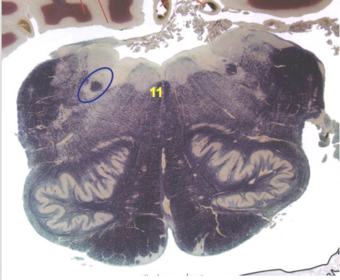

| Head of caudate | |

| Anterior commissure | |

| Thalamus | |

| Substantia nigra | |

| Optic tract | |

| Dentate nucleus | |

| Pons | |

| Longitudinal pontine fibers | |

| Uncus | |

| Superior cerebellar peduncle | |

| Red nucleus | |

| Corticospinal tract (dark) | |

| Pontine nuclei (pale) | |

| Transverse pontine fibers (dark) | |

| Inferior olive | |

| CTT | |

| Medial lemniscus | |

| Nucleus cuneatus | |

| Superior colliculus | |

| Inferior colliculus | |

| Optic nerve | |

| Cerebellum | |

| 4th ventricle | |